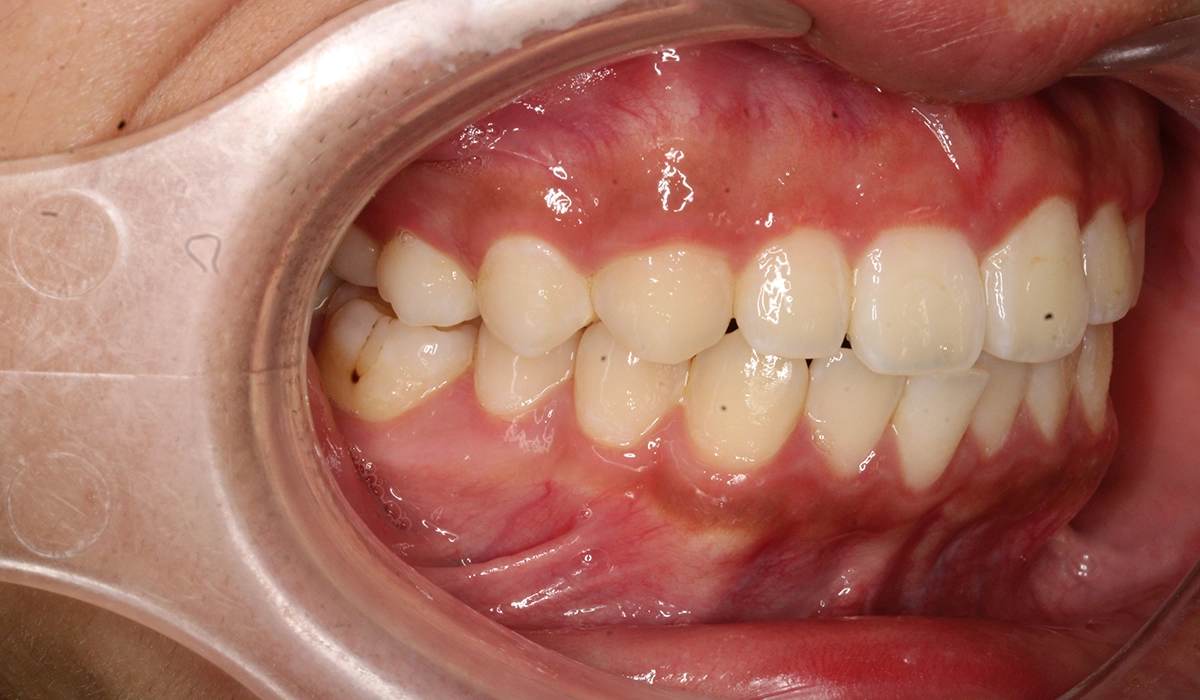

術後:右側